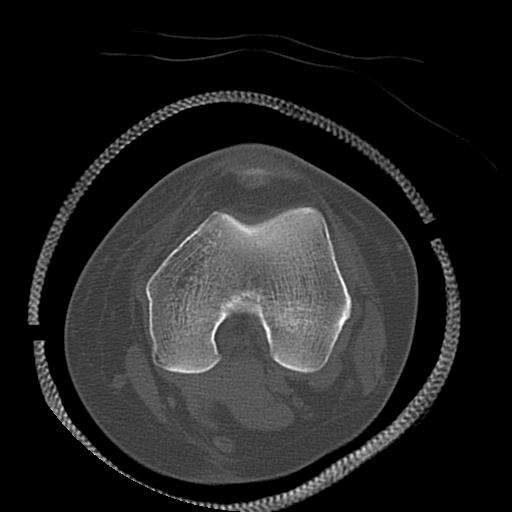

91983 11/16 左膝 2R 11/18 2R 55歳男性 脛骨骨切り術